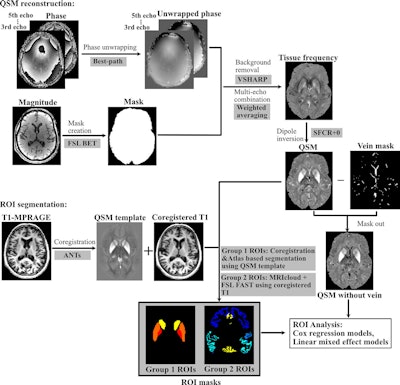

Processing pipeline for quantitative susceptibility mapping (QSM) reconstruction and region-of-interest (ROI) segmentation MRICloud is cloud-based medical image processing software (mricloud.org). ANT = advanced normalization tool, BET = brain extraction tool, FAST = functional MRI of the brain automated segmentation tool, FSL = functional MRI of the brain software library, MPRAGE = magnetization-prepared rapid gradient-echo, SFCR+0 = structural feature–based collaborative reconstruction with auto-referencing to central cerebrospinal fluid, VSHARP = variable radius sophisticated harmonic artifact reduction for phase data.Processing pipeline for quantitative susceptibility mapping (QSM) reconstruction and region-of-interest (ROI) segmentation MRICloud is cloud-based medical image processing software (mricloud.org). ANT = advanced normalization tool, BET = brain extraction tool, FAST = functional MRI of the brain automated segmentation tool, FSL = functional MRI of the brain software library, MPRAGE = magnetization-prepared rapid gradient-echo, SFCR+0 = structural feature–based collaborative reconstruction with auto-referencing to central cerebrospinal fluid, VSHARP = variable radius sophisticated harmonic artifact reduction for phase data.Images and caption courtesy of the RSNA.